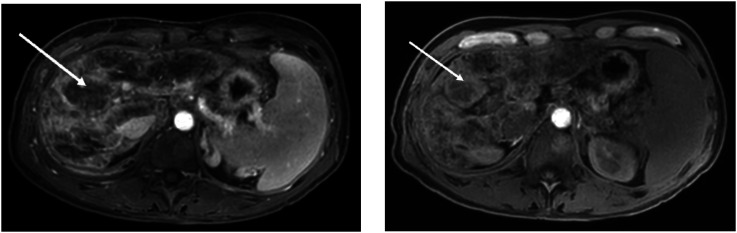

Case presentationDescription of a patient with a progressive destructive lung disease resembling pleuroparenchymal fibroelastosis, liver cirrhosis and bone marrow changes. Genetic workup identified a rare heterozygous coding variant in the TERT (telomerase reverse transcriptase) gene c.472 C>T; p.(Leu158Phe) and telomere length testing revealed significant telomere shortening, supporting the diagnosis of telomere biology disorder (TBD).DiscussionTBD is an underrecognized cause of interstitial lung disease (ILD). It is a heterogeneous disease that can affect different organs, including lungs, liver and bone marrow. Genetic testing in ILD is crucial for early diagnosis, risk assessment, and family screening. Identifying this variant enables targeted genetic testing for relatives, allowing preventive measures and lifestyle modifications.